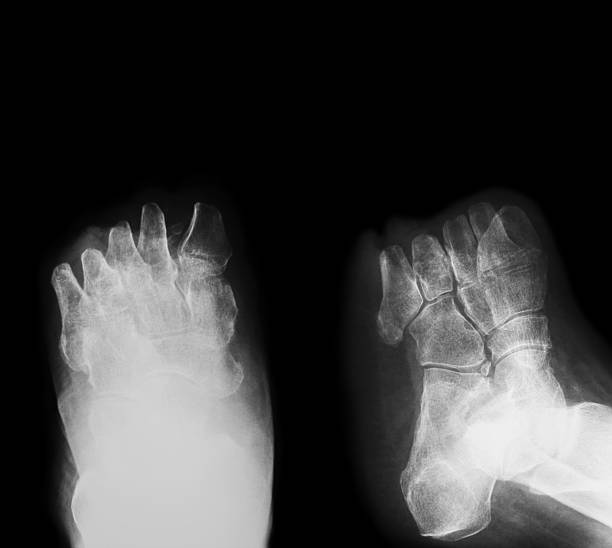

Волога гангрена – агресивна та інфікована

Волога гангрена розвивається, коли в уражену ділянку тіла потрапляє інфекція. Її причинами можуть бути глибокі травми, занедбані рани, тискові виразки чи відсутність лікування сухої форми.

Основні ознаки:

- Різкий, гнильний запах.

- Набряк, почервоніння, пухирі з рідиною.

- Посилення болю.

- Гнійні виділення.

- Загальна інтоксикація – лихоманка, слабкість, падіння тиску.

При вологій гангрені інфекція завжди поширюється тілом. Цей стан потребує втручання – і негайного. Навіть при локалізованому ураженні він може викликати септичний шок.